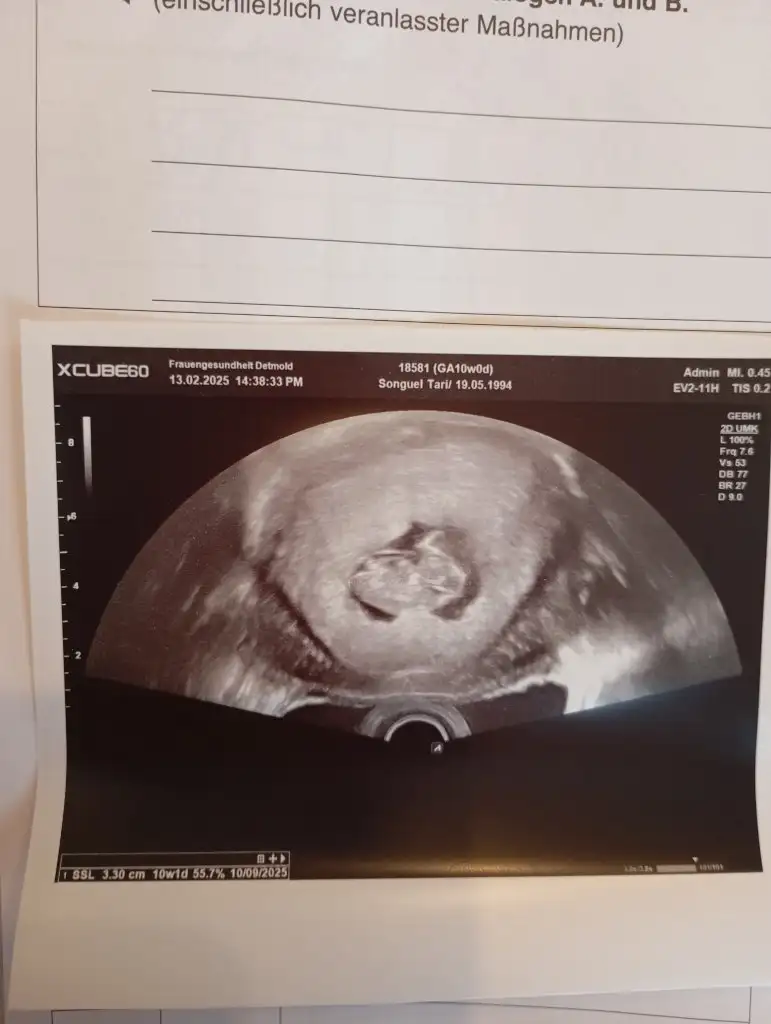

ErkekKızlar 10 haftalık hamileyim cinsiyet tahmini sizce nedir

Kese yuvarlak kız gibiAy bende çok merak ettim vajinal 8 haftalık